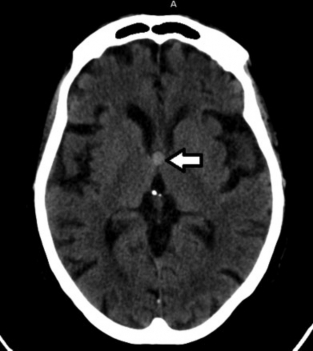

Constituyen variantes anatómicas que se presentan en la línea media derivando de alteraciones del desarrollo del septum pellucidum (SP).7 En TC y RM se los aprecia con densidad o señal similar al LCR (►Figs. 1, 2, 3).7

Resonancia magnética (RM) de cerebro, corte axial ponderado en T2: la flecha señala al cavum septum pellucidum (CSP) entre las astas frontales de los ventrículos laterales.